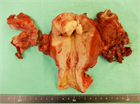

1. 下腹部痛・発熱・炎症反応上昇・膿瘍など画像所見・原因病原体の検出をもって診断する。